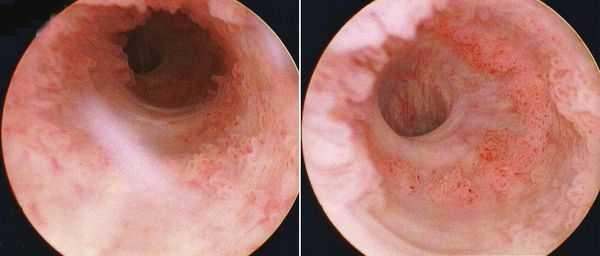

Ведущую роль в установлении диагноза рака мочевого пузыря, как и много десятилетий тому назад, продолжает играть цистоскопия [7]. Важным аспектом использования цистоскопии является обеспечение визуального контроля за выполнением биопсии мочевого пузыря. Однако, по данным цистоскопии нельзя определить стадию заболевания, особенно затруднительно при дифференциальной диагностике между Т1 и Т2 стадиями. В последние десятилетия ведётся интенсивный поиск опухолевых маркеров рака мочевого пузыря, обнаружение которых в моче можно было бы рассматривать как показание для проведения цистоскопии [7].

- Эндоскопия мочевого пузыря. Обязательным визуализирующим методом диагностики служит цистоскопия, при которой производится уточнение локализации, размеров, внешнего вида опухоли, состояния устьев мочеточников. Эндоскопическое исследование может дополняться биопсией, позволяющей провести морфологическую верификацию новообразования.